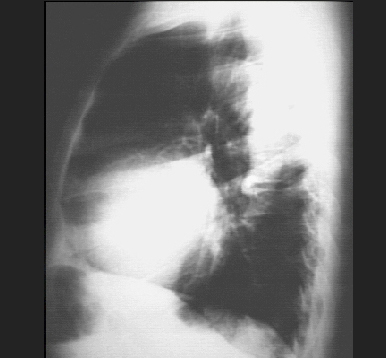

The lateral view shows left ventricular enlargement, as evidenced by posterior displacement of the left ventricular shadow.